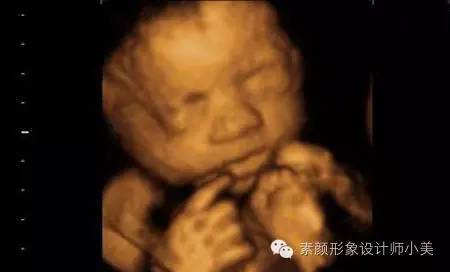

胎儿发育:

现在胎儿开始频繁地胎动了,身长已经接近14厘米,体重大约200克。这时候是您和宝宝沟通的大好机会,宝宝在您的肚子里面可什么都知道,您只要和他/她说话,他就会做出相应的反应。如果是女孩,她的阴道,子宫,输卵管都已经各就各位;如果是男孩,宝宝的生殖器已经清晰可见。